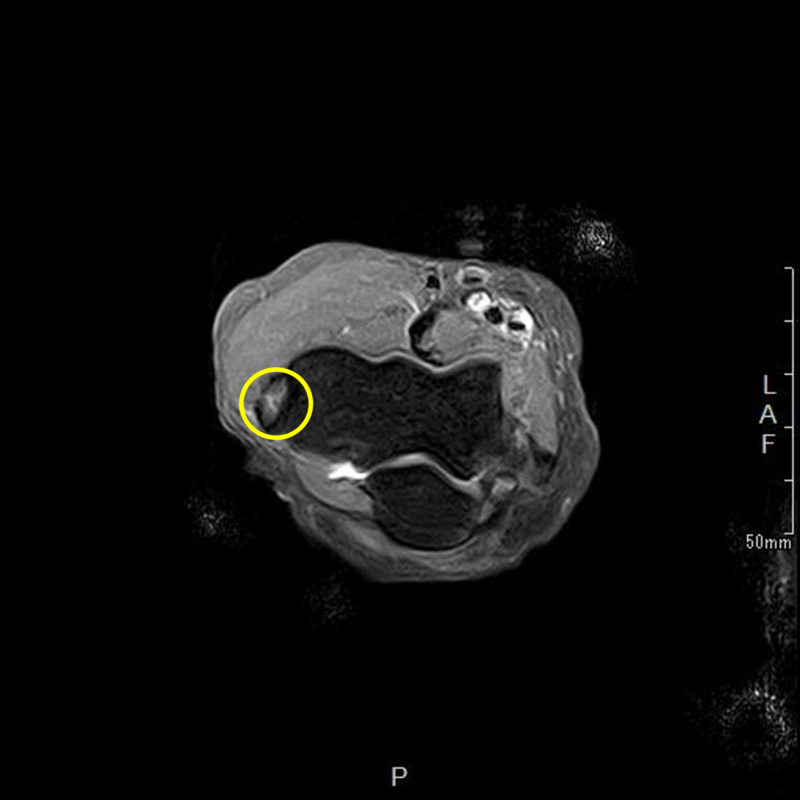

肘の離断性骨軟骨炎(以下:OCD:osteochondritis dissecans)は上腕骨小頭という部位に好発することが多いです。

OCDは成長期の代表的なスポーツ障害であり、野球などといった投球・投擲動作を行うスポーツ選手で投球側に発生することが多いです。大半は10-12歳で発症し成長期における有病率は2-3%と頻度は少ないが進行するとスポーツにみならず、日常生活お支障をきたすことが多い怪我です。そのため、早期発見・早期治療が重要となります。

OCDを発見するにはレントゲンや超音波検査で上腕骨小頭軟骨下骨の状態を観察します。

軟骨下骨の不整像が軽微か不明の場合はMRI検査を行いOCDの確定診断を行います。

症例提示

12歳・男性・スポーツは野球(週2回/4年間)

2024年3月頃から外傷誘因なく疼痛出現。

2024年4月上旬、他院受診して超音波検査で軟骨が剝がれていると診断を受けたが経過観察のみ。

2024年5月、当院受診。レントゲン撮影をして離断性骨軟骨炎と診断されてリハビリ開始。

リハビリでは、徒手療法(マッサージ)・運動療法(筋力トレーニング ストレッチ)・物理療法を実施していましたが、

疼痛消失には至らず、組織修復を目的に体外衝撃波を実施しました。

体外衝撃波(拡散型圧力波治療)は、週1回の頻度で3回実施しました。

現在は、リハビリテーションでトレーニング継続中です。